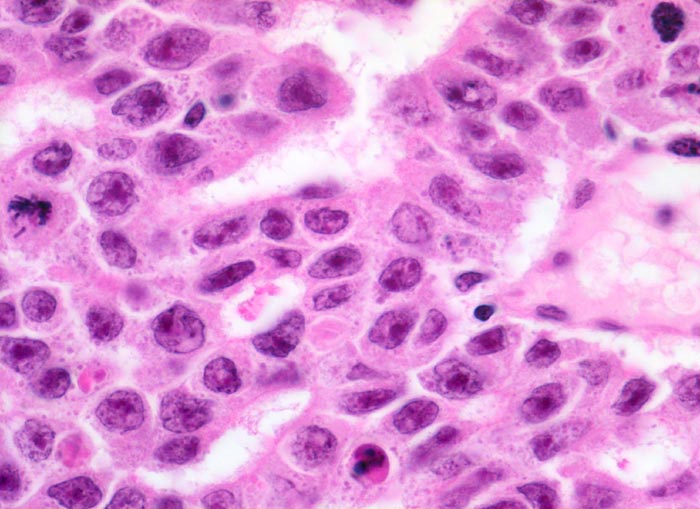

Histologisch bilden die Tumorzellen solide Zellplatten, Drüsen oder papilläre Strukturen mit Einblutungen und Nekrosen. Die Tumorzellen sind polygonal, kubisch oder zylindrisch, haben reichlich Zytoplasma und unscharfe Zellgrenzen. Die grossen Kerne haben grob verklumptes Chromatin und enthalten oft mehrere sehr grosse unregelmässige Nukleolen. Gefässeinbrüche und eine testikuläre intratubuläre Neoplasie sind in der Tumorumgebung häufig nachweisbar

Morphologische Merkmale:

• Sehr grosse, pleomorphe und hyperchromatische Zellkerne mit prominenten Nukleolen.

• Mitosen und Apoptosen.